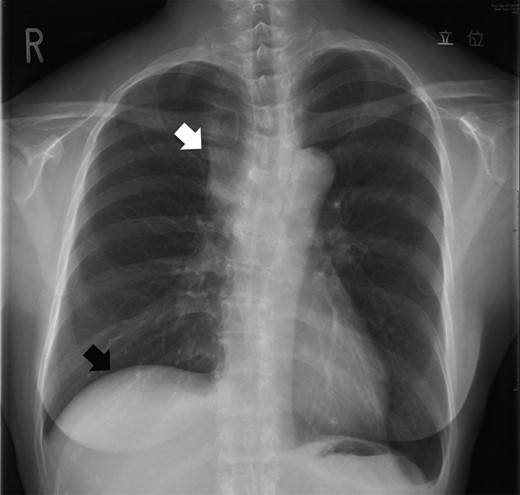

A 61-year-old woman was admitted to our hospital with edema of both upper limbs and face. Blood examination results were almost normal, but, carcinoembryonic antigen was slightly elevated (7.1 ng/ml). A chest X-ray on admission showed an enlarged superior mediastinum and right diaphragmatic elevation (Fig. 1). Enhanced computed tomography (CT) of the chest showed an invasive anterior mediastinal tumor, 6.0 × 3.7 cm in size, invading to bilateral brachiocephalic veins and superior vena cava (SVC) with intraluminal tumor thrombus (Fig. 2a–c). Percutaneous CT-guided biopsy of the tumor was performed immediately after admission, and this tumor was diagnosed as adenocarcinoma, with the suspicion of primary thymic carcinoma or metastatic thymic tumor from gastrointestinal malignancies (Fig. 3a,b). Immunohistochemical examination showed that the tumor cells were positive for cytokeratin 20 and caudal type homeobox 2. Systemic workups revealed no other primary sites or any distant metastases, and she was finally diagnosed as having locally advanced primary thymic adenocarcinoma. Induction CRT was provided to induce a reduction of the tumor with the aim of complete resection. She was administered chemotherapy consisting of carboplatin and paclitaxel on a weekly basis and was treated concurrently with thoracic radiotherapy (50 Gy; 2.0 Gy × 25 fractions). The chest CT after induction CRT demonstrated a reduction of the tumor (partial response: 43% reduction in tumor diameter) and improvement of venous tumor thrombus (Fig. 2d–f). During the CRT, symptomatic SVC syndrome gradually improved, and no severe acute toxicity was observed.

A chest X-ray on admission showed an enlarged superior mediastinum (white arrow) and right diaphragmatic elevation (black arrow).